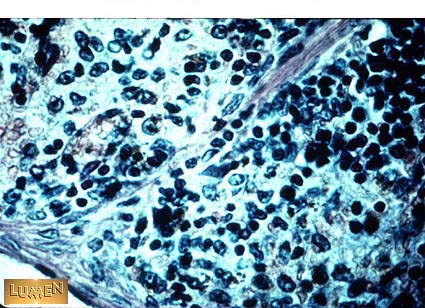

What tissue (seen here) separates splenic sinusoids?

Red Pulp / Cords of Billroth